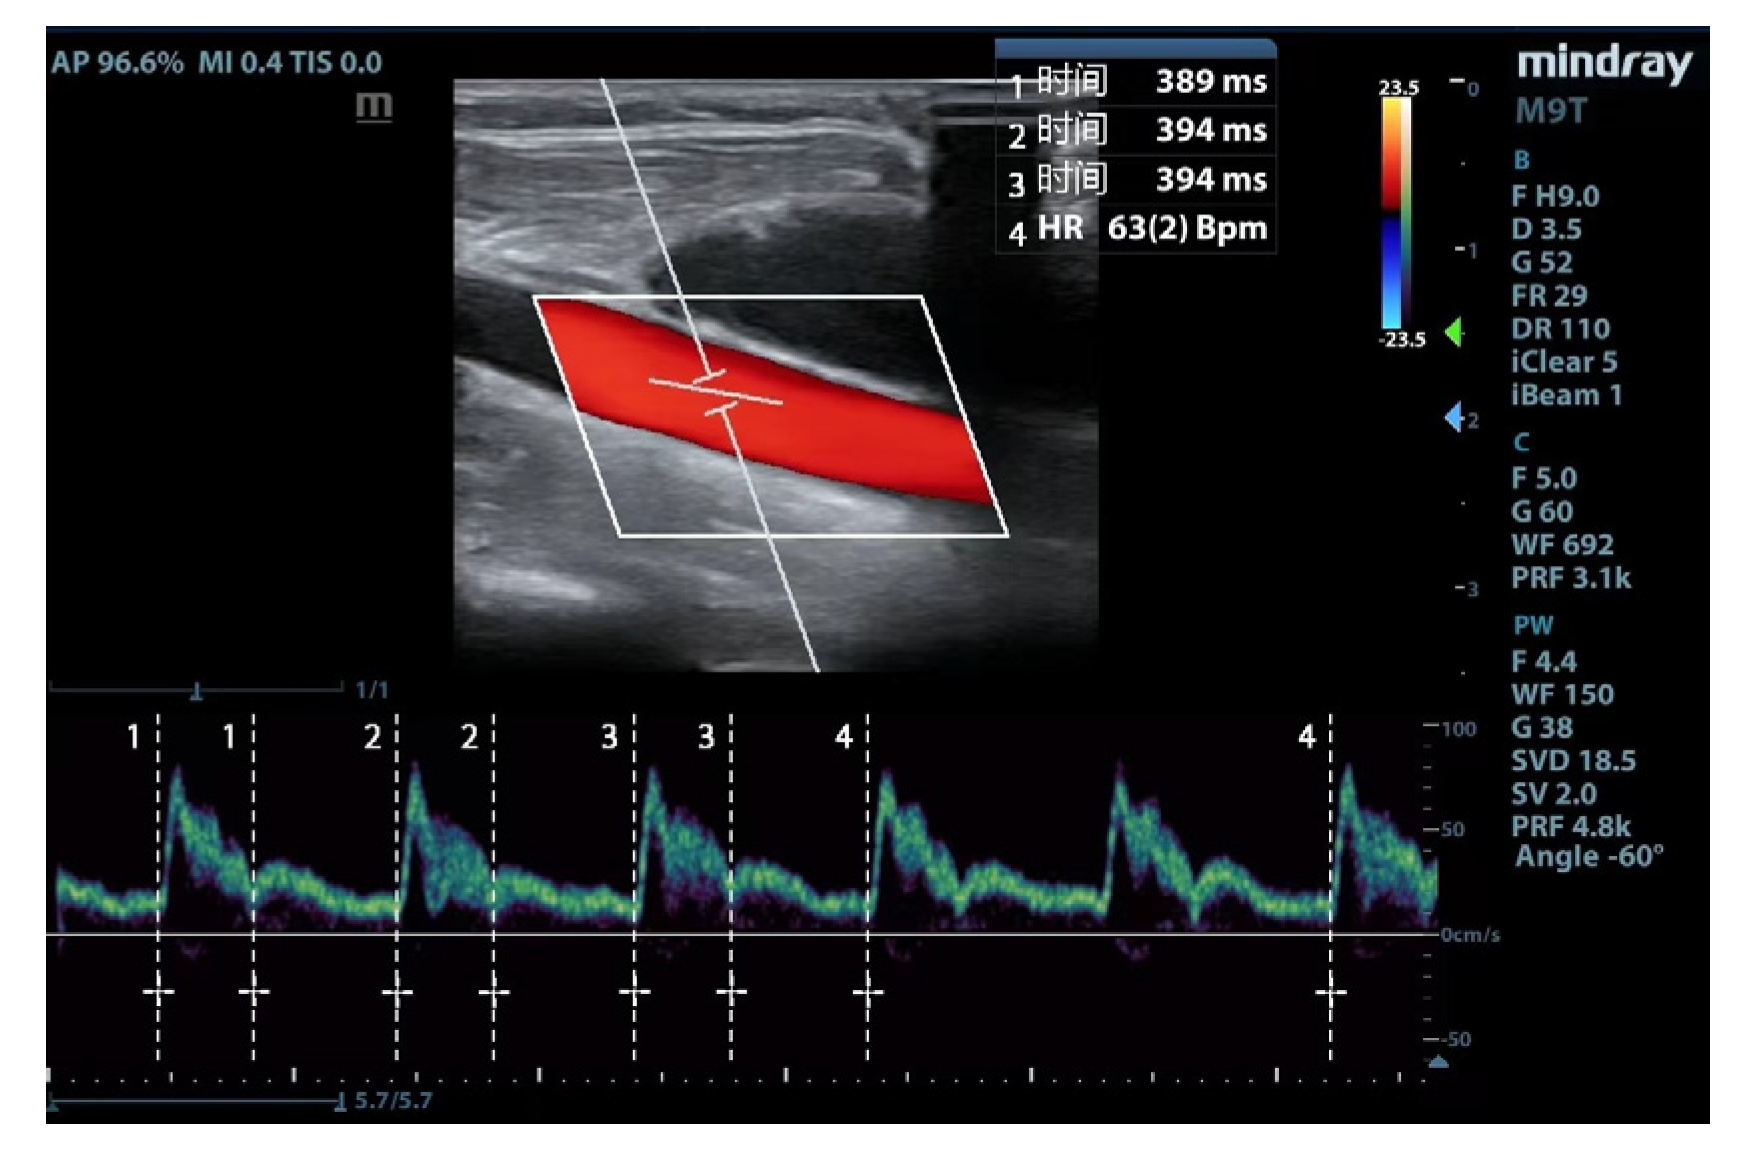

2.5. Carotid ultrasonography

The ultrasonic parameters were measured using a portable ultrasound device (Mindray Medical Systems, Shenzhen, China). The following scanning protocol acquired images of the common carotid artery: (1) a high-frequency line array transducer was placed transversely at the lower border of the thyroid cartilage, ensuring the common carotid artery was centered on the screen; (2) the long axis B-mode image of the common carotid artery was obtained with the probe marker pointing towards the patient’s head; (3) the sample volume was placed at the center of the arterial vessel, and the cursor angle was adjusted parallel to the direction of blood flow, with an insonation angle of ≤60°, approximately 2 cm proximal to the carotid bifurcation; (4) a satisfactory spectrum is displayed and frozen by adjusting the optimal sampling volume and angle, then measurement was performed by the caliper function on the machine. Flow time (FT) was measured from the beginning of the systolic upstroke to the dicrotic notch. HR was obtained by measuring the interval between the beginning of two consecutive Doppler flow upstrokes. The average of three consecutive cycles was recorded once stability was achieved and the quality reached an acceptable level (Figure 1). FTc was calculated using the Wodey formula: FTc = FT + [1.29 × (HR - 60)] [15].

Figure 1. Carotid Doppler waveform.